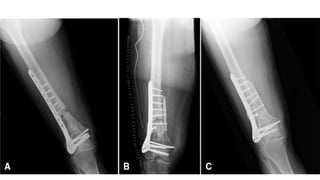

This document discusses femoral fractures, categorized by their location and severity, with classifications such as Garden classification. It outlines the types of fractures, including valgus impacted, non-displaced, partially displaced, and fully displaced, along with their surgical treatment options. Additionally, it briefly describes distal femur fractures, which occur just above the knee joint.